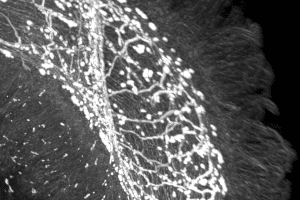

Conhecidos como ADNec, estes anéis genéticos flutuam livremente no núcleo da célula, permitindo que as células tumorais intensifiquem rapidamente a expressão dos genes do cancro, alterem a sua forma e sobrevivam em ambientes que de outra forma lhes seriam hostis.

A investigação permitiu agora identificar o “motor oculto desta adaptabilidade”, o ADN extracromossómico.